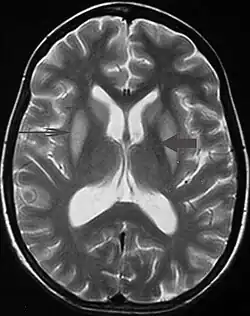

| Axial fat-saturated T2-weighted image showing hyperintensity in the pons with sparing of the peripheral fibers, the patient was an alcoholic admitted with a serum Na of 101 treated with hypertonic saline, he was left with quadriparesis, dysarthria, and altered mental status | |

It can be diagnosed clinically in the appropriate context, but may be difficult to confirm radiologically using conventional imaging techniques. Changes are more prominent on MRI than on CT, but often take days or weeks after acute symptom onset to develop. Imaging by MRI typically demonstrates areas of hyperintensity on T2-weighted images.[30]